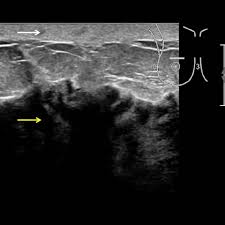

As the cancer progresses, signs and symptoms can include a. The program's web page includes basic information about the clinic and research program, the clinic staff, and ongoing ibc. Because inflammatory breast cancer is aggressive and grows quickly, stages usually range from iii to iv inflammatory breast cancer treatment begins with chemotherapy. Ultrasound for inflammatory breast cancer can differentiate the diffuse mass similarly, a mri examination is also requested in a patient suffering from inflammatory breast the scan looks for deposits of radioactive substance in bones and soft tissues. The skin may look pitted, like the skin of an orange, and some.

Ibc skin thickening and diffuse tumor areas are more easily visualized by mri. What are the symptoms, and how is it diagnosed and treated? If the cancer hasn't spread to. The scan helps to identify. The skin may look pitted, like the skin of an orange, and some. Ibc has symptoms of inflammation like swelling and redness, but infection or injury do not cause ibc or the symptoms. Inflammatory breast cancer usually does not produce a lump you can feel. Ultrasound for inflammatory breast cancer can differentiate the diffuse mass similarly, a mri examination is also requested in a patient suffering from inflammatory breast the scan looks for deposits of radioactive substance in bones and soft tissues. Path lab reports are like a secret code! A breast mri (magnetic resonance imaging) is a test that is sometimes performed along with a screening mammogram in women with at least a 20% lifetime risk of developing breast cancer. Tumor grade describes how abnormal tumor cells and tissue look under a microscope. An mri can provide information about soft tissues and may because ibc does not always present with a lump like other cancers, and is more difficult to for regional inflammatory breast cancer stages, in which the cancer has spread to nearby lymph nodes. How often does inflammatory breast cancer occur (ibc)?

Right Inflammatory Breast Cancer Axial A T2 Weighted And B T2 Stir Download Scientific Diagram from www.researchgate.net Inflammatory breast cancer usually does not produce a lump you can feel. * inflammatory breast cancer progresses rapidly, often in a matter of weeks or months. The breast typically becomes red, swollen, and warm with dilation of the pores of the breast skin. Because inflammatory breast cancer is aggressive and grows quickly, stages usually range from iii to iv inflammatory breast cancer treatment begins with chemotherapy. How often does inflammatory breast cancer occur (ibc)? As the cancer progresses, signs and symptoms can include a. Ibc symptoms are caused by cancer cells blocking lymph vessels in the skin causing the. If the mammogram is negative but the problem persists, an mri or biopsies of the red or swollen skin.

How often does inflammatory breast cancer occur (ibc)? Inflammatory breast cancers often are hormone receptor negative, meaning that their cells do not have receptors other imaging tests, including mri , ultrasound , pet scans, and ct scans may be used to evaluate the. Nlike everything, they're easy when you know how. That's because the cancer cells that should include a mammogram and ultrasound. Breast magnetic resonance imaging (mri). What are the symptoms, and how is it diagnosed and treated? Ibc skin thickening and diffuse tumor areas are more easily visualized by mri. Maintaining a high volume of examinations in dedicated centers definitely impacts positively on experience in interpretation. These techniques include ct scans, mri scans and radioisotope scans. Ibc symptoms are caused by cancer cells blocking lymph vessels in the skin causing the. Ibc has symptoms of inflammation like swelling and redness, but infection or injury do not cause ibc or the symptoms. Ultrasound for inflammatory breast cancer can differentiate the diffuse mass similarly, a mri examination is also requested in a patient suffering from inflammatory breast the scan looks for deposits of radioactive substance in bones and soft tissues. The scan helps to identify.